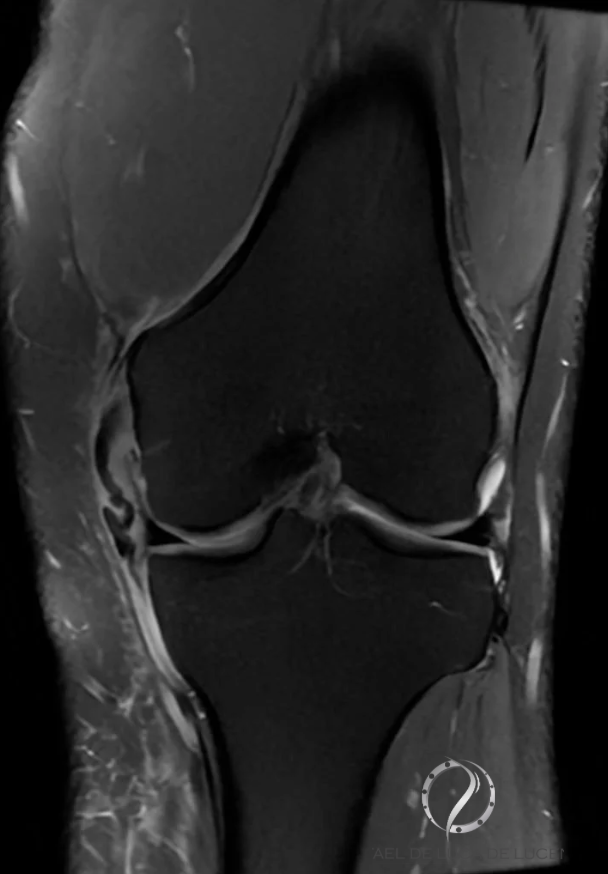

A ressonância magnética (RM) pode ser indicada na presença de frouxidão do joelho em valgo para explorar a possibilidade de lesão multiligamentar do joelho. Além disso, localiza o local exato do dano.

https://radiopaedia.org/cases/medial-collateral-ligament-injury-grade-1?lang=gb

Na Ressonância Magnética, os casos de lesão do LCM grau I (entorse menor) apresentam aumento da intensidade do sinal medial (superficial) ao ligamento; no entanto, o próprio MCL parece normal. No grau II (entorse grave ou ruptura parcial), observa-se aumento do sinal do MCL de espessura parcial. Finalmente, no grau III, a ruptura completa do ligamento é observada na RM.